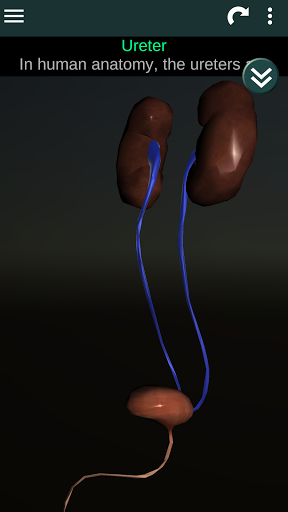

Показує 3D анатомічну модель основні органи людського тіла та опис кожного з них.

* Описи кожного органу.